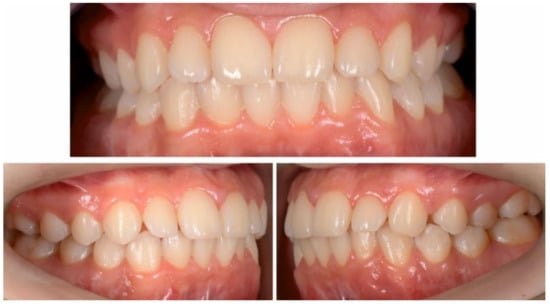

2.2.1. Initial Examination